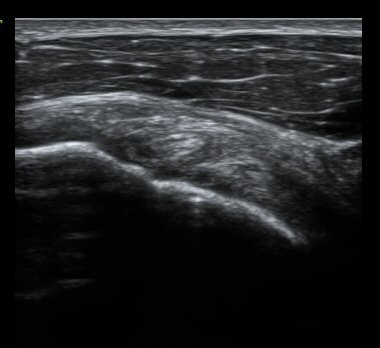

À̵ιڱٰí¶û¿¡¼­ À̵ιڱÙÀÌ Á¤»óÀûÀ¸·Î °üÂûµÇ°í ƯÀÌ ¼Ò°ßÀ» º¸ÀÌÁö ¾ÊÀ½(±×¸² 2).